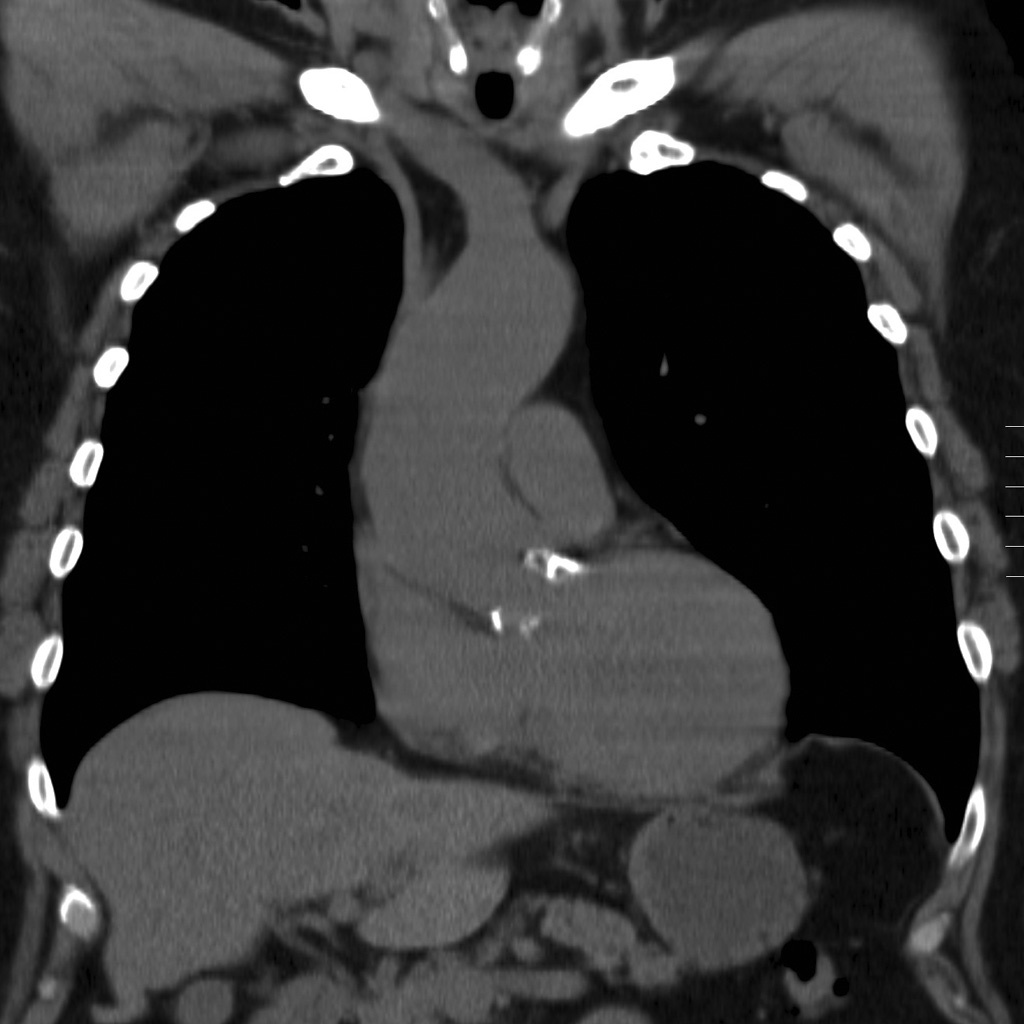

Intraaortic Balloon Pump (IABP)

Tip should be located just distal to the takeoff of the left subclavian artery (LSA) and be 2–4 cm below aortic knob. Inflation may be seen during diastole.

The balloon should be located in the proximal descending aorta, just below the origin of the left subclavian artery. On a chest radiograph, it should be at the level of the AP window. This ideally results in the balloon terminating just above the splanchnic vessels 3.